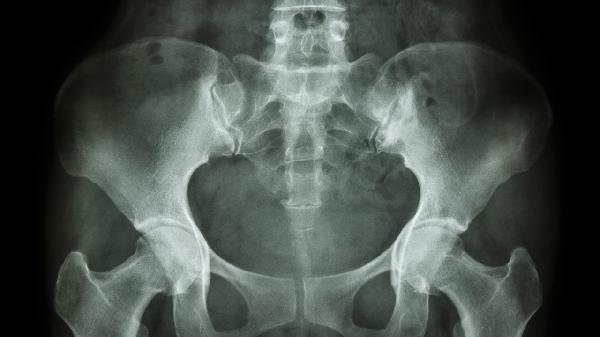

怎樣矯正骨盆前傾

矯正骨盆前傾可通過改善姿勢(shì)、強(qiáng)化核心肌群、拉伸緊張肌肉、調(diào)整日常習(xí)慣及物理治療等方式實(shí)現(xiàn)。骨盆前傾通常由久坐、肌肉失衡、不良姿勢(shì)、妊娠或外傷等因素引起。